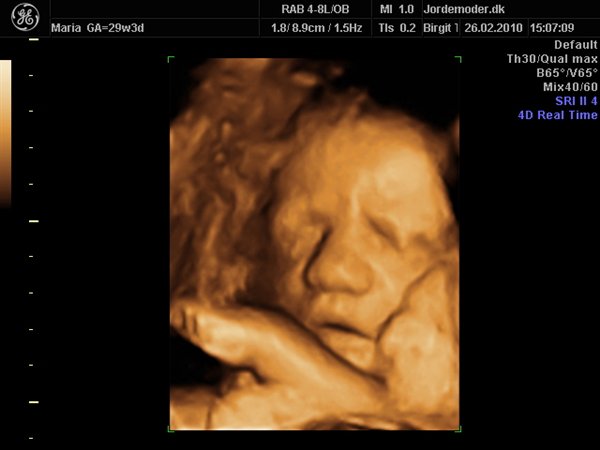

Idag har vi jo set lille pigen i 3d/4d, og hvor var det bare den mest fantastiske oplevelse..

Hun er bare så smuk og dejlig, med de fineste ballon kinder..

Her kommer lige lidt billeder af vores smukke datter..